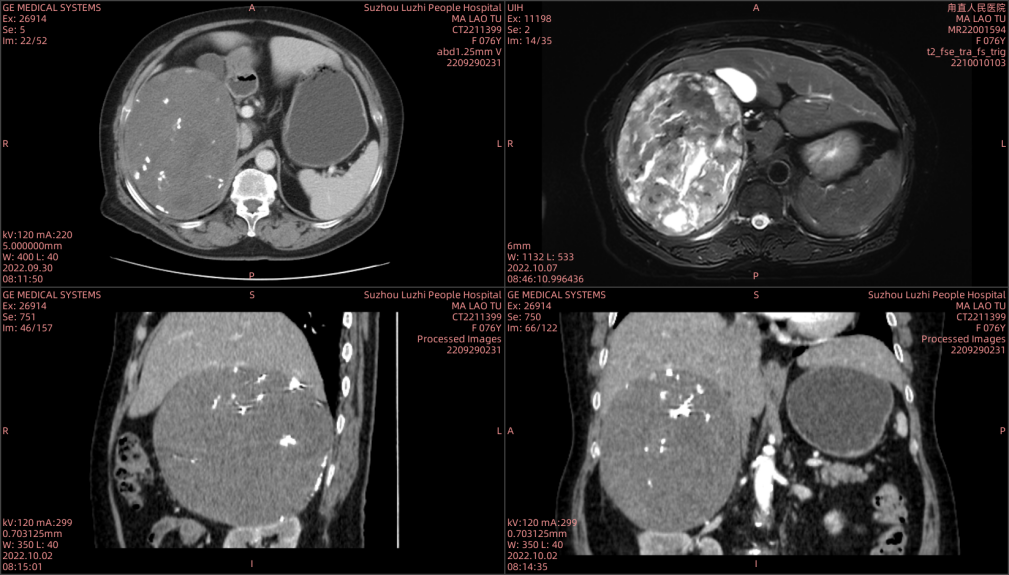

CT及MR示:腹膜后巨大占位

来自苏州吴中区甪直的马老太已过古稀之年,一年前发现自己腹部右侧微微隆起,但当时她觉得没有不舒服,也没当回事,更没有到医院做进一步检查。直到今年10月份,她感觉肚子隐隐作痛,还伴有腹胀、疲倦的感觉,便和家属到当地医院检查,发现果然有问题:右侧腹膜后巨大占位,大小约15cmx12cm。考虑肾上腺皮质腺癌。

然而,想要切除这个像“排球”大的巨大肿瘤并不容易!住院后经检查发现,这个肿瘤来源不明,而且严重挤压右肾及肝脏,与右侧肾上腺关系密切,手术切除肿瘤并保护各重要脏器手术难度巨大。泌尿外科团队立即组织术前全院会诊,邀请普外科、影像科、麻醉科、心内科、重症医学科、内分泌科、肾内科专家进行多学科进行病例讨论。影像科张卫国主任表示,经过详细的检查,初步考虑这是来源于肾上腺的肿瘤,恶性肿瘤的可能性很大,但是从影像检查发现,肿瘤包膜较为完整,除了手术切除之外,其他的治疗方法难以奏效;麻醉科侯永恒主任表示,考虑肾上腺来源的肿瘤有可能是嗜铬细胞瘤,这种肿瘤会影响血压变化,手术切除过程中血压会出现波动,风险极大。巨大肿瘤周围不但血管密布,还与周围的肝、肾及肠道粘连,这无疑大大增加了手术的风险和难度。为了尽可能减少创伤和风险从而达到能够切除肿瘤的要求,科室讨论后决定为她进行手术,完整切除肿瘤并保护各重要脏器,尤其是尽量不损伤右侧肾脏及肝脏。